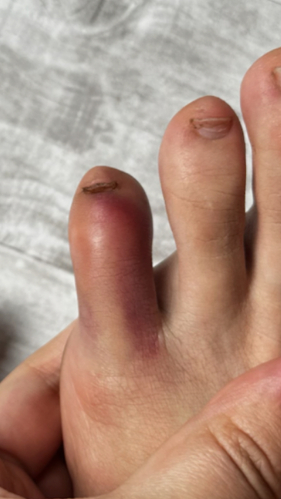

Гнойный панариций

Жалоба на резкую, пульсирующую боль, распирание, нарушение функции

Назначено: 1 процедура ФДТ REVIXAN (монотерапия)